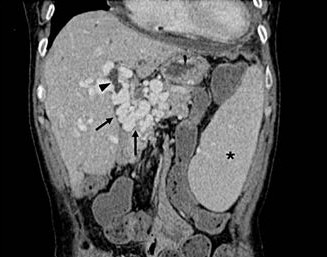

• Imaging “Mini-Atlas” of Vascular Liver Diseases

Rita Trovisco, Prof. Manuela França

48-59

DOI: https://doi.org/10.60591/crspmi.560